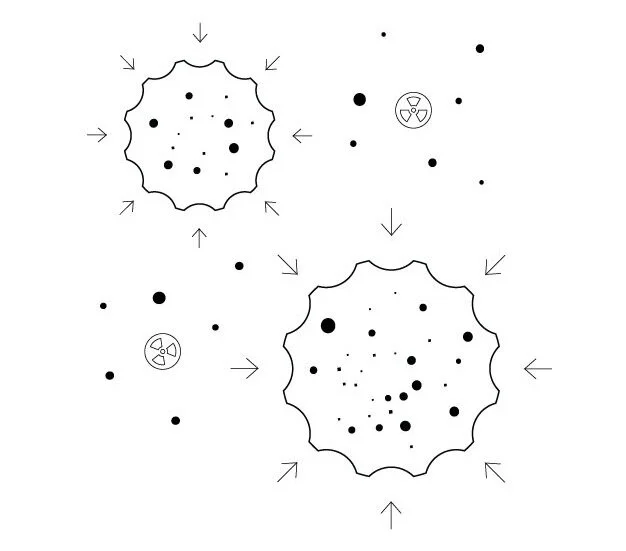

Prof. Juliette Legler of Utrecht University reported on animal studies showing that microplastics are able to enter the placenta, and the developing organs of the fetus. This is extremely disturbing considering that early development in the womb can affect later life. Assistant Prof. Nienke Vrisekoop, also at Utrecht, found that microplastics have the ability to kill immune cells. A three month study concluded that macrophages were attacking microplastics as if they were pathogens (enemy to immune system, foreign to body homeostasis). This also implies that there is a natural occurring / resulting state of inflammation, whether it be minor or major, inflammation is directly correlated to disease, most popularly, cancer.

Microplastics affect immune cells, creating a reaction and inflammation

– Assistant Prof. Nienke Vrisekoop, Utrecht University